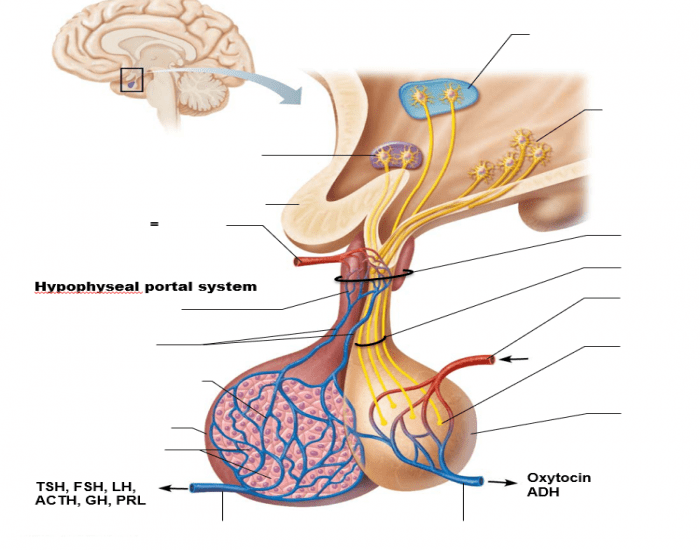

Как работает центр насыщения в гипоталамусе: визуальные иллюстрации